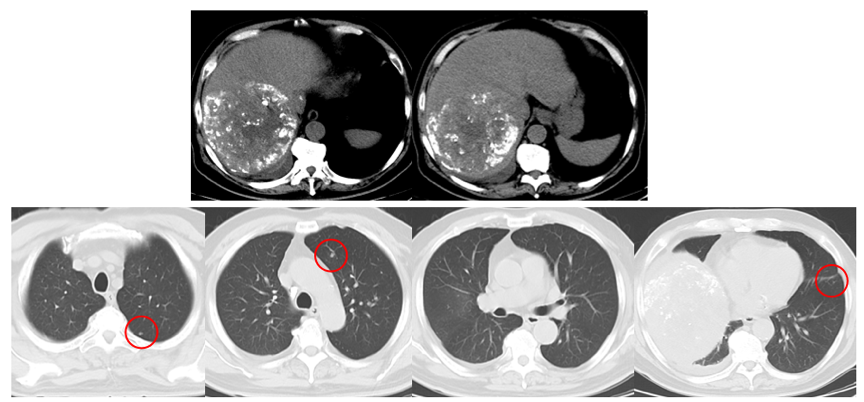

2020年5月24日,第1次TACE术后1月复查CT示,肝脏碘油沉积良好,肺部小结节出现,考虑肺部转移灶(图2)。CNLC分期转为Ⅲb期。

图2.2020年5月24日肝脏和肺部CT

2020年5月26日行第2次TACE治疗,并于2020年5月29日给予索拉非尼治疗。2020年7月15,2次TACE及索拉非尼1.5个月后复查CT提示,肝部病灶稳定,碘油沉积良好;肺部结节较前明显增大,处于进展状态(图3)。AFP由552ng/ml升至>1210ng/ml。

图3.2020年7月15日胸部和肝脏CT

2020年8月6日(瑞戈非尼 卡瑞利珠单抗,1个疗程),胸部CT示,肺部病灶较前明显好转(图4)。AFP由>1210ng/ml降至579ng/ml。

图4.2020年8月6日胸部CT